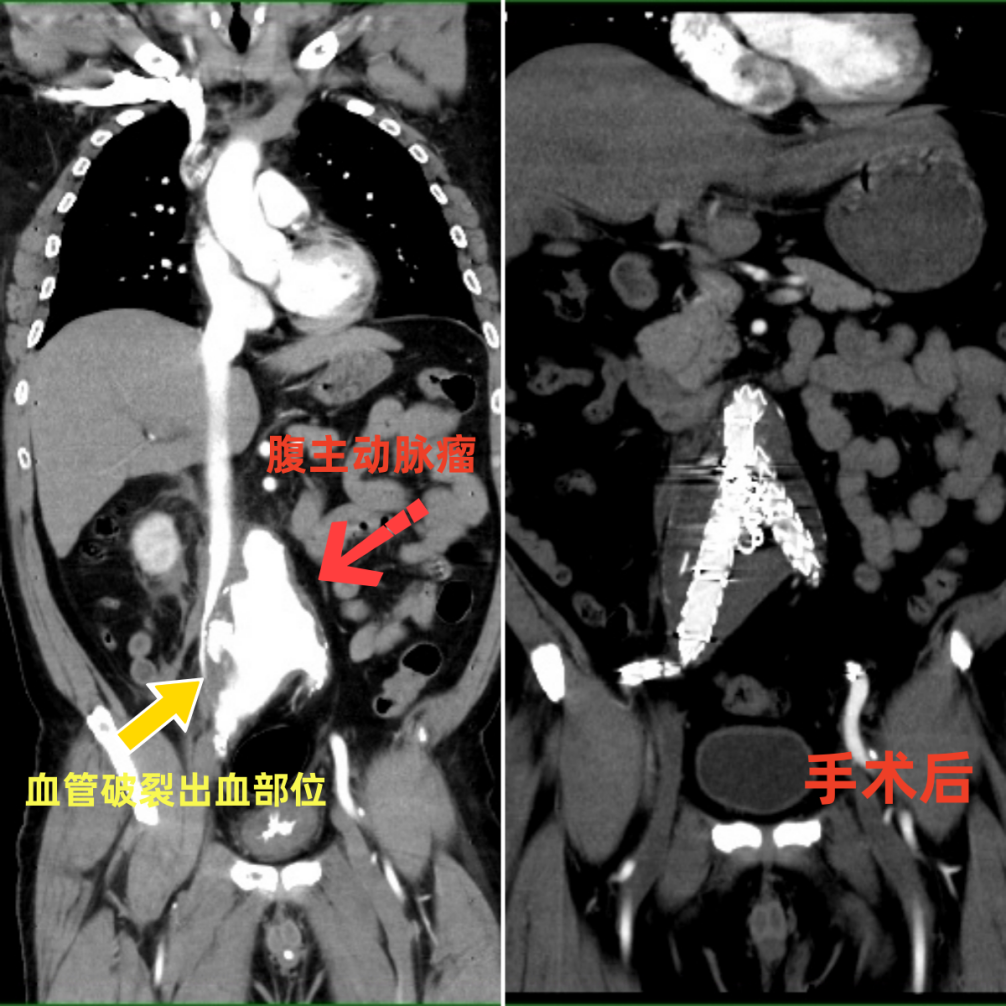

手术前CTA检查。

手术前后CT情况。